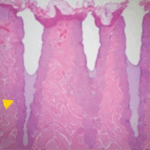

Immediately after treatment – Fractional laser energy creates micro-ablated columns to stimulate cellular regrowth. The surrounding healthy tissue promotes rapid healing.

Two days post-treatment – Skin is healing on the surface and creating new dermal collagen. This will continue for up to six months. The improved skin quality will make for a more youthful appearance.